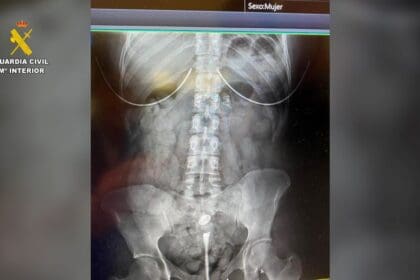

La Guardia Civil pudo establecer, a partir de las declaraciones de la víctima y de los detenidos que, en algún momento, le suministraron una sustancia química para anular su voluntad y someterlo. Aprovechando esta circunstancia, accedieron a su teléfono móvil y a sus cuentas bancarias utilizando el reconocimiento facial biométrico para realizar

Cuadro de texto: Nota de prensamúltiples transferencias. Posteriormente, los detenidos realizaron retiradas de efectivo en cajeros de localidades cercanas.